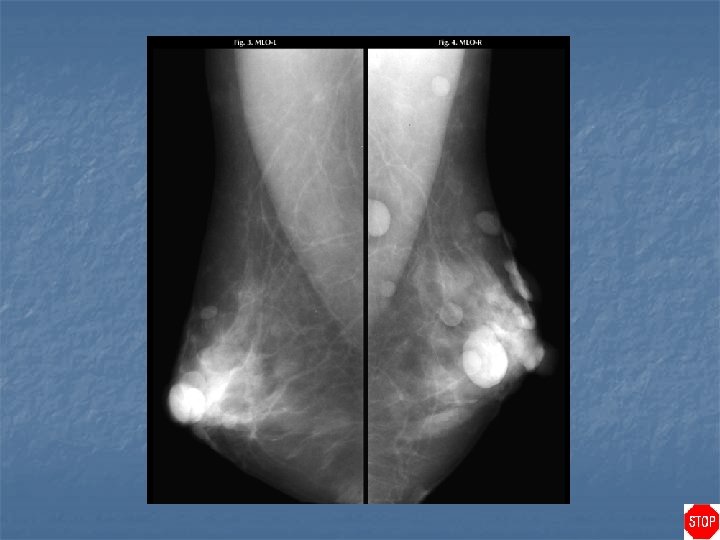

Rheumatoid arthritis n Case findings: n n Enlarged dense axillary lymph nodes DDX of enlarged axillary lymph nodes: n n n BCA with lymph node metastasis Lymphoma HIV RA TB, sarcoidosis Benign reactive nodal hyperplasia

Metallic deposits in axillary nodes from RA gold injections

Case directory Rheumatoid arthritis n DDX of calcified axillary lymph nodes: MC metastasis (ovarian, mucinous tumors) n RA with gold treatment n Treated lymphoma n